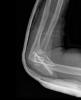

Fractura impactada de húmero .

Fractura de húmero.

Fractura compleja de húmero.